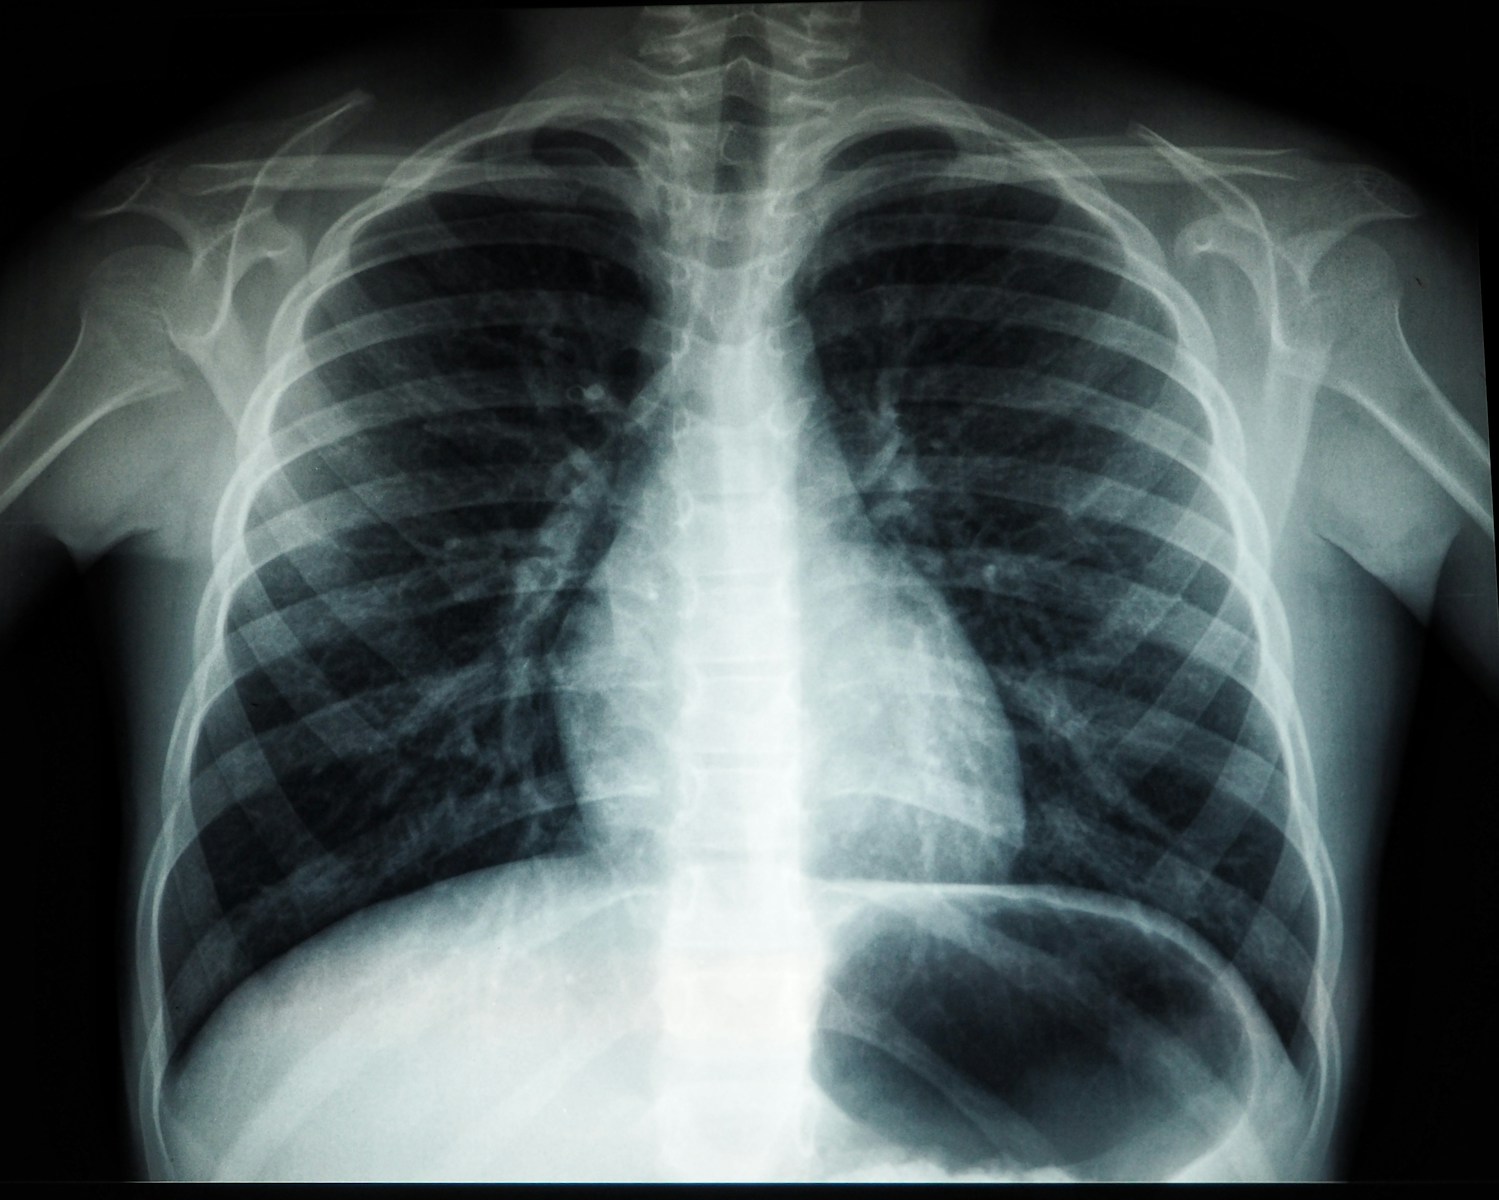

Een andere gevaarlijke oorzaak is een longembolie. Daarbij blokkeert een bloedprop de bloedtoevoer naar de longen. Dit kan scherpe pijn geven bij ademhalen of hoesten. Soms hoest iemand zelfs bloed op.

Dr. Cannon benadrukt dat hartaanvallen vaker voorkomen dan mensen denken. Veel mensen herkennen de signalen niet direct. Longembolieën zijn zeldzamer, maar vereisen directe medische hulp.